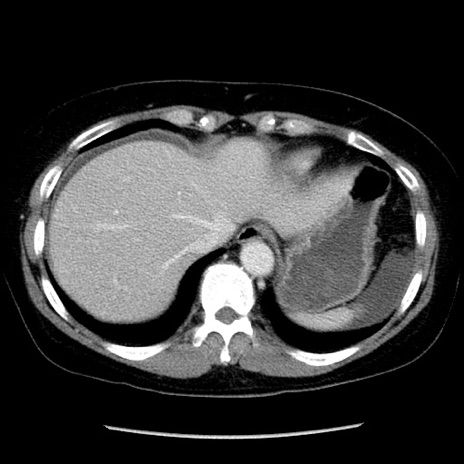

冠状断像